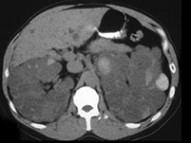

女,52岁,腰部酸胀,根据影像图像,判断其最可能的诊断 ( )A、肾脓肿B、肾盂癌伴出血C、肾细胞癌D、多囊肾E、多房性肾囊肿

问题 女,52岁,腰部酸胀,根据影像图像,判断其最可能的诊断 ( )

选项 A、肾脓肿 B、肾盂癌伴出血 C、肾细胞癌 D、多囊肾 E、多房性肾囊肿

答案 D